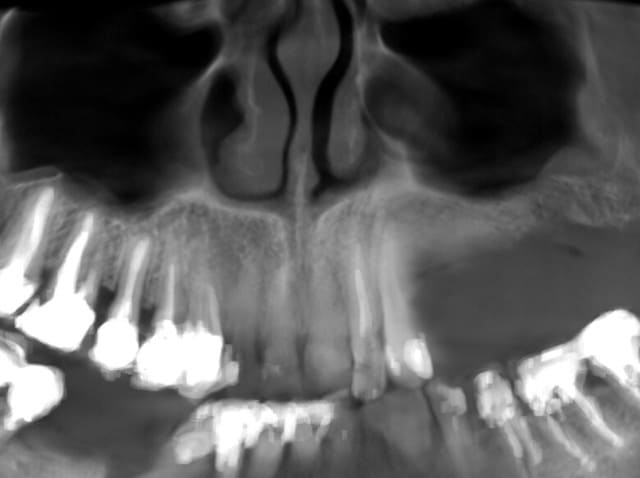

en voilà un autre; question:

ci joints quelques clichés.

T'as une pano, car les coupes dont pas super explicite

ci-joint la coupe panoramique